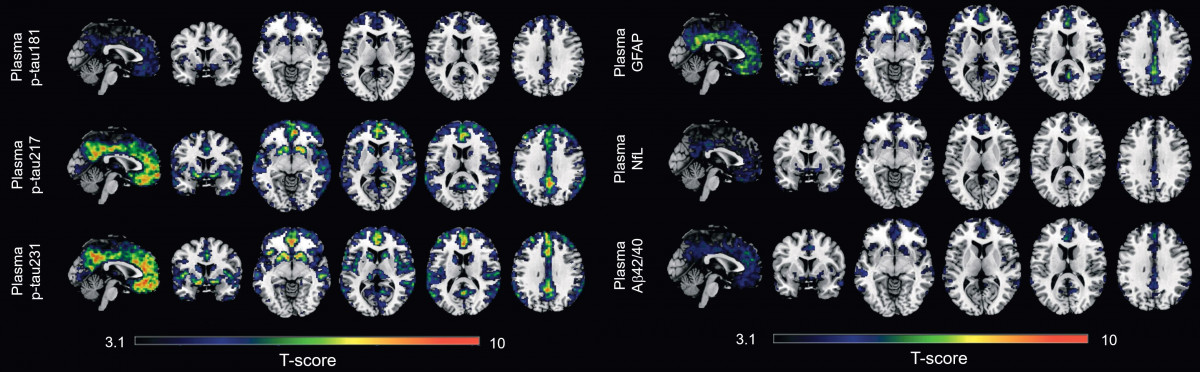

En colaboración con la Universidad de Gotemburgo, los investigadores han desarrollo el nuevo biomarcador en sangre p-tau231 y lo han comparado con otros cinco biomarcadores en sangre --los p-tau181, p-tau217, Ab42/40, GFAP y NfL--, previamente estudiados en la fase sintomática de la enfermedad de Alzheimer.

Este es el primer estudio que investiga todos estos biomarcadores en la fase preclínica de la enfermedad de Alzheimer, y los resultados muestran que p-tau231 y p-tau217 son los mejores biomarcadores en sangre para detectar los primeros signos de acumulación de amiloide en el cerebro.

El estudio indica que los biomarcadores en sangre p-tau231 y p-tau217 mostraron la asociación más fuerte con la retención de amiloide en regiones de acumulación temprana en el cerebro y se asociaron con aumentos longitudinales en la captación de esta proteína en individuos sin patología amiloide manifiesta al comenzar el estudio.